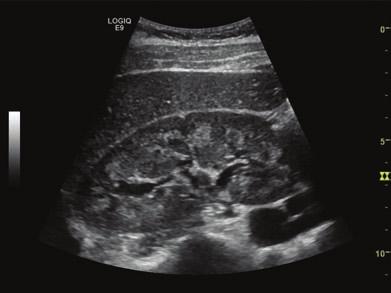

Philips hd5 ultrasound color Doppler scan